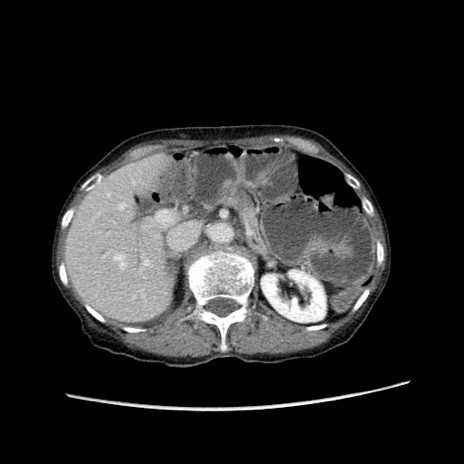

症例25(横断像)

【症例】80歳代女性

【主訴】胸のつかえ感

【現病歴】約9時間前に食後から胸のつかえた感じあり、嘔吐あり、来院。

【既往歴】胃癌(全摘)、胆摘、虫垂炎

【身体所見】心窩部に圧痛あり、反跳痛なし。

【データ】WBC 5700、CRP 0.05